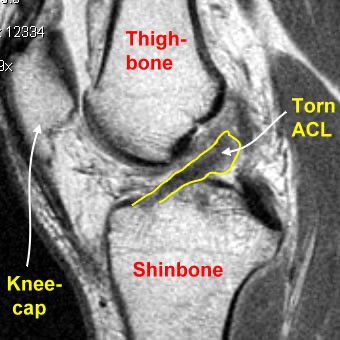

Traditional ACL repair involves stitching the torn ligament back to its original attachment. This technique relies on the ligament’s natural healing capacity. However, the ACL has a limited blood supply, which makes natural healing unreliable and often incomplete—especially in active individuals.

ACL reconstruction, on the other hand, replaces the damaged ligament with a graft. This graft is usually taken from the patient’s own hamstring tendon, patellar tendon, or quadriceps tendon, or in some cases from a donor (allograft). Over time, the graft integrates with the knee and functions as a new, strong ligament—offering superior stability and durability.